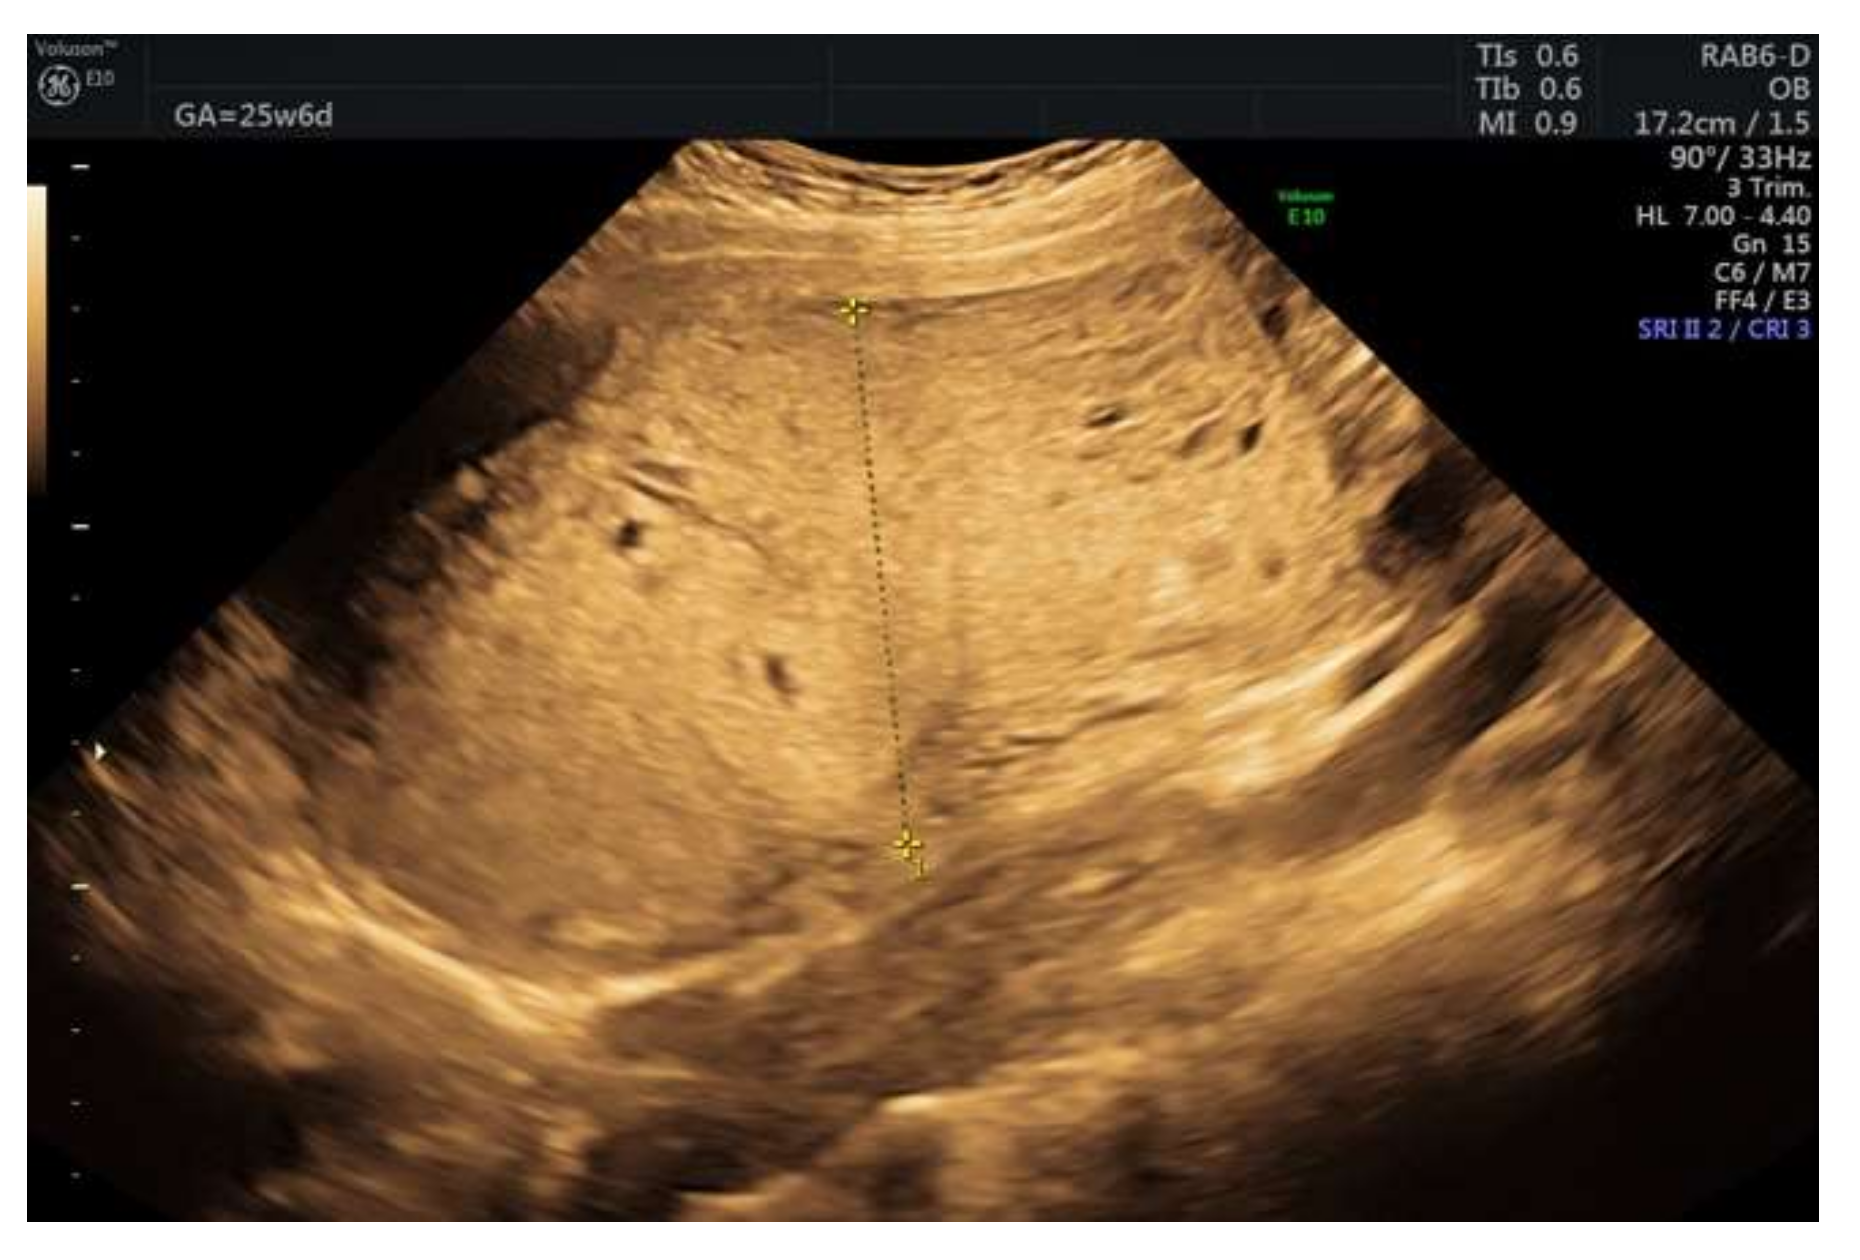

3. Case Report